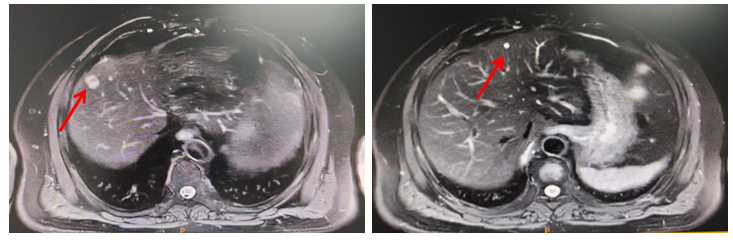

腹部MRI(2019年3月11日)示:肝内两处异常信号,考虑转移可能(图1)。

腹部MRI(2023年2月22日)示:肝脏多发异常信号,考虑转移可能性大。